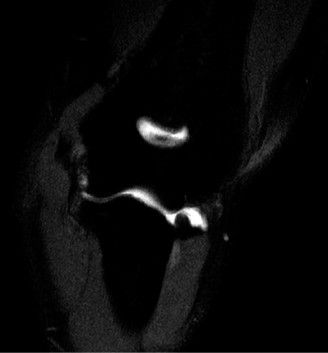

CT arthrograms of the patient’s left shoulder are shown in Figure 2–56. CRP is <3, ESR 45. The patient continues to have pain, so you decide to perform arthroscopic biopsy to obtain tissue cultures. Frozen sections show <5 PMNs per hpf, and Gram stains are all negative.

Figure 2–56

The correct answer is (B). Figure shows contrast under the glenoid component. Given the patient’s normal inflammatory markers and frozen sections combined with continued pain and loosening on CT, infection with P. acnes(an organism that is very difficult to isolate) should be investigated by holding any cultures for at least 2 weeks to see if it will eventually grow. Chocolate agar (Choice C) is mainly used for growing species such as H. influenzae and Neisseria meningitidis not P. acnes. A is incorrect since the patient’s cell count and frozen sections are clearly abnormal, therefore referral to pain clinic would not be appropriate. However, Choice D would be too aggressive an approach given that no organisms have been isolated, frozen sections show <5 PMNs per hpf, and the patient has relatively normal inflammatory markers.